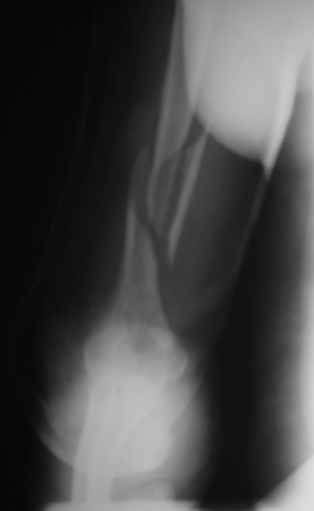

Теперь непосредственно по больному. Лечим функциональной повязкой, добились вот чего (приложение). Будем признательны за дальнейший комментарий - мое мнение, что можно продолжить без операции.